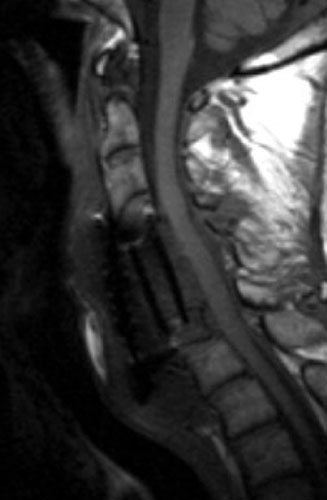

73 y.o male, s/p C5-6 corpectomy and anterior fusion of C4-6 with anterior plating for gradual bilateral upper extremity weakness and eventually bowel dysfunction. 5 days after the surgery, while in the hospital, the patient was struck by a food services cart. Noting after that incident, more pain and a new 'click' sound in the neck, further imaging was obtained.

Immediate post-op radiograph demonstrate good position of the graft and fixation plate.